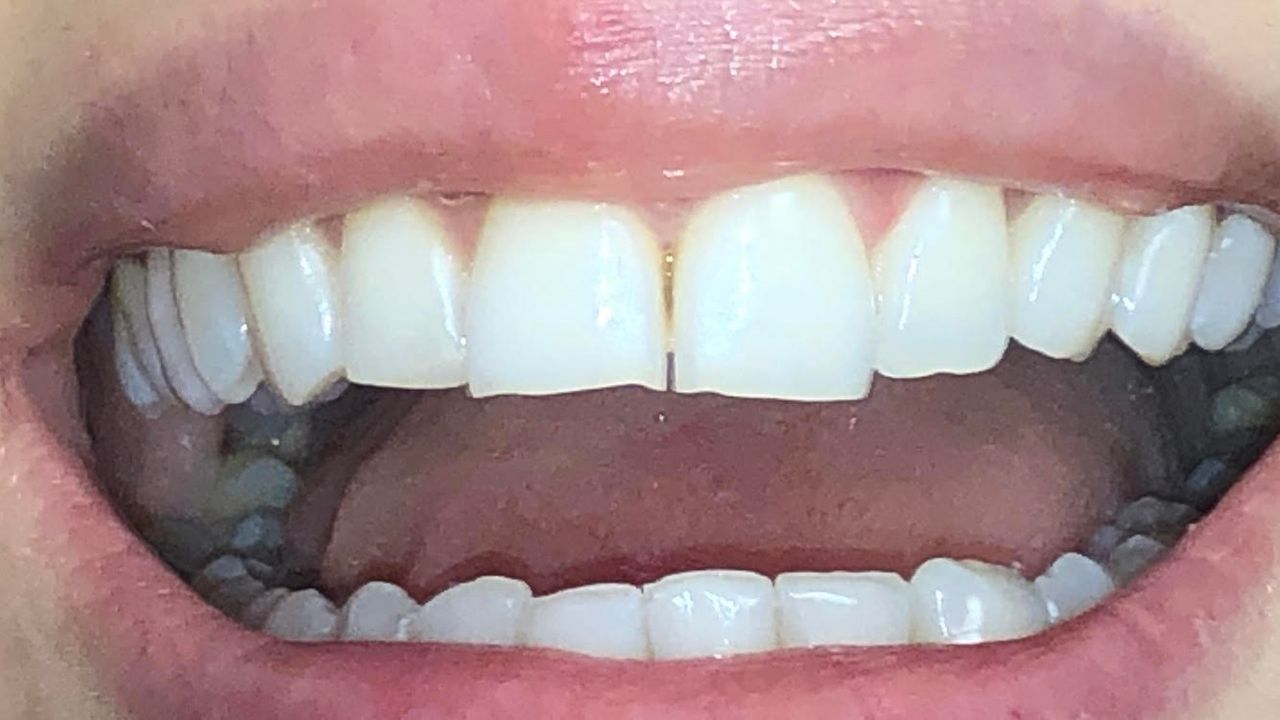

Foto e video

Il Dottor Luca Strazioso ha qualità rare; mi ha ascoltata attentamente sin dal primo appuntamento, con la sua pazienza, competenza e professionalità durante ogni seduta ha ricostruito il mio sorriso, mi ha ridato la sicurezza che ormai avevo perduto. Posso affermare di essere rinata grazie alle sue mani, alla sua intelligenza e sensibilità. Inoltre, la Signora Antonella, assistente alla poltrona, è assolutamente insostituibile e generosa. Infinitamente grata ad entrambi.